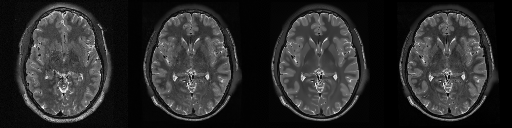

HCP T2w dataset

We utilize images from the publicly available Human Connectome Project (HCP) [51] T2-weighted (T2w) images dataset for the task of compressed sensing, which contains brain images from 47 patients. The HCP dataset includes cross-sectional images of the brain taken at different levels and angles.

Compressed sensing

We train a flow-based model from scratch on 10,000 randomly sampled images, utilizing the ncsnpp architecture [9] with minor adaptations for grayscale images. We employ compression rates , meaning . The measurement operator is given by a subsampled Fourier matrix, whose sign patterns are randomly selected. We evaluate our reconstruction algorithm’s performance on 200 randomly sampled test images.

We present the quantitative and qualitative results of compressed sensing in Tab. 1 and Fig. 4, respectively. As shown in Tab. 1, our method consistently achieves the best performance across varying compression rates . In Fig. 4, our method produces reconstructions that are more faithful to the original images, with fewer artifacts, leading to higher accuracy and clearer details.